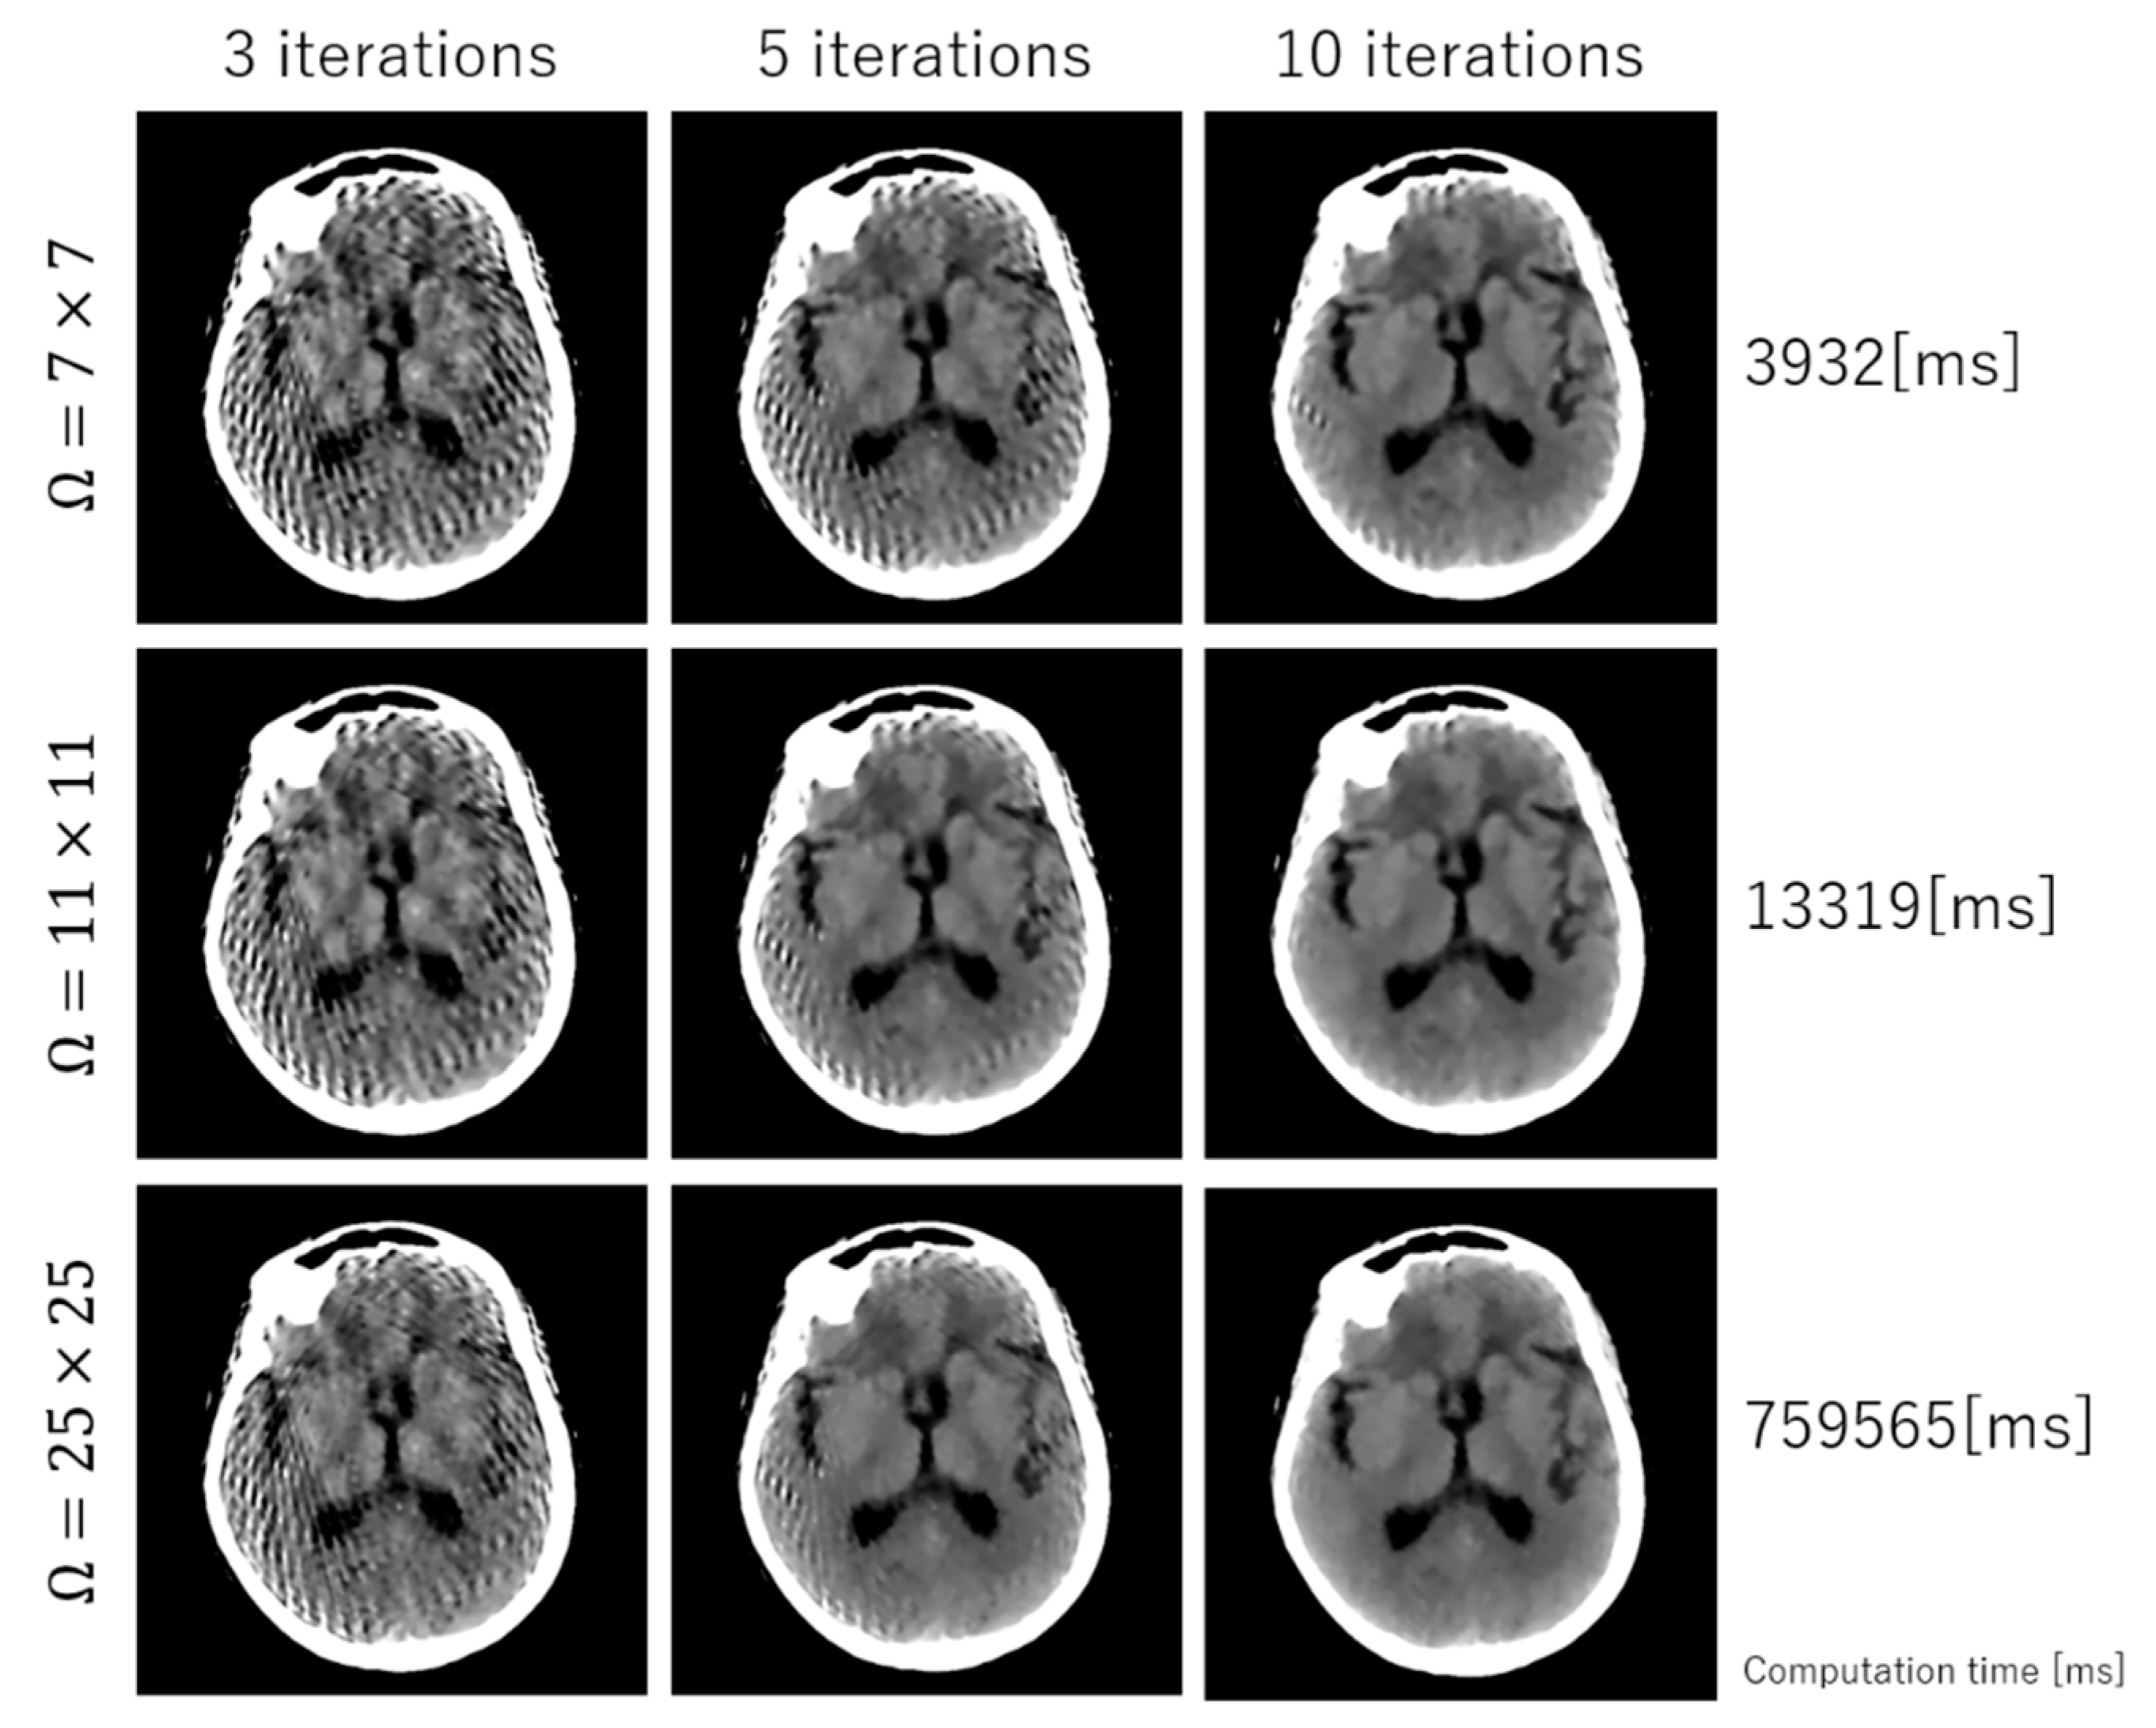

2. Methodology

3. Experimental Results